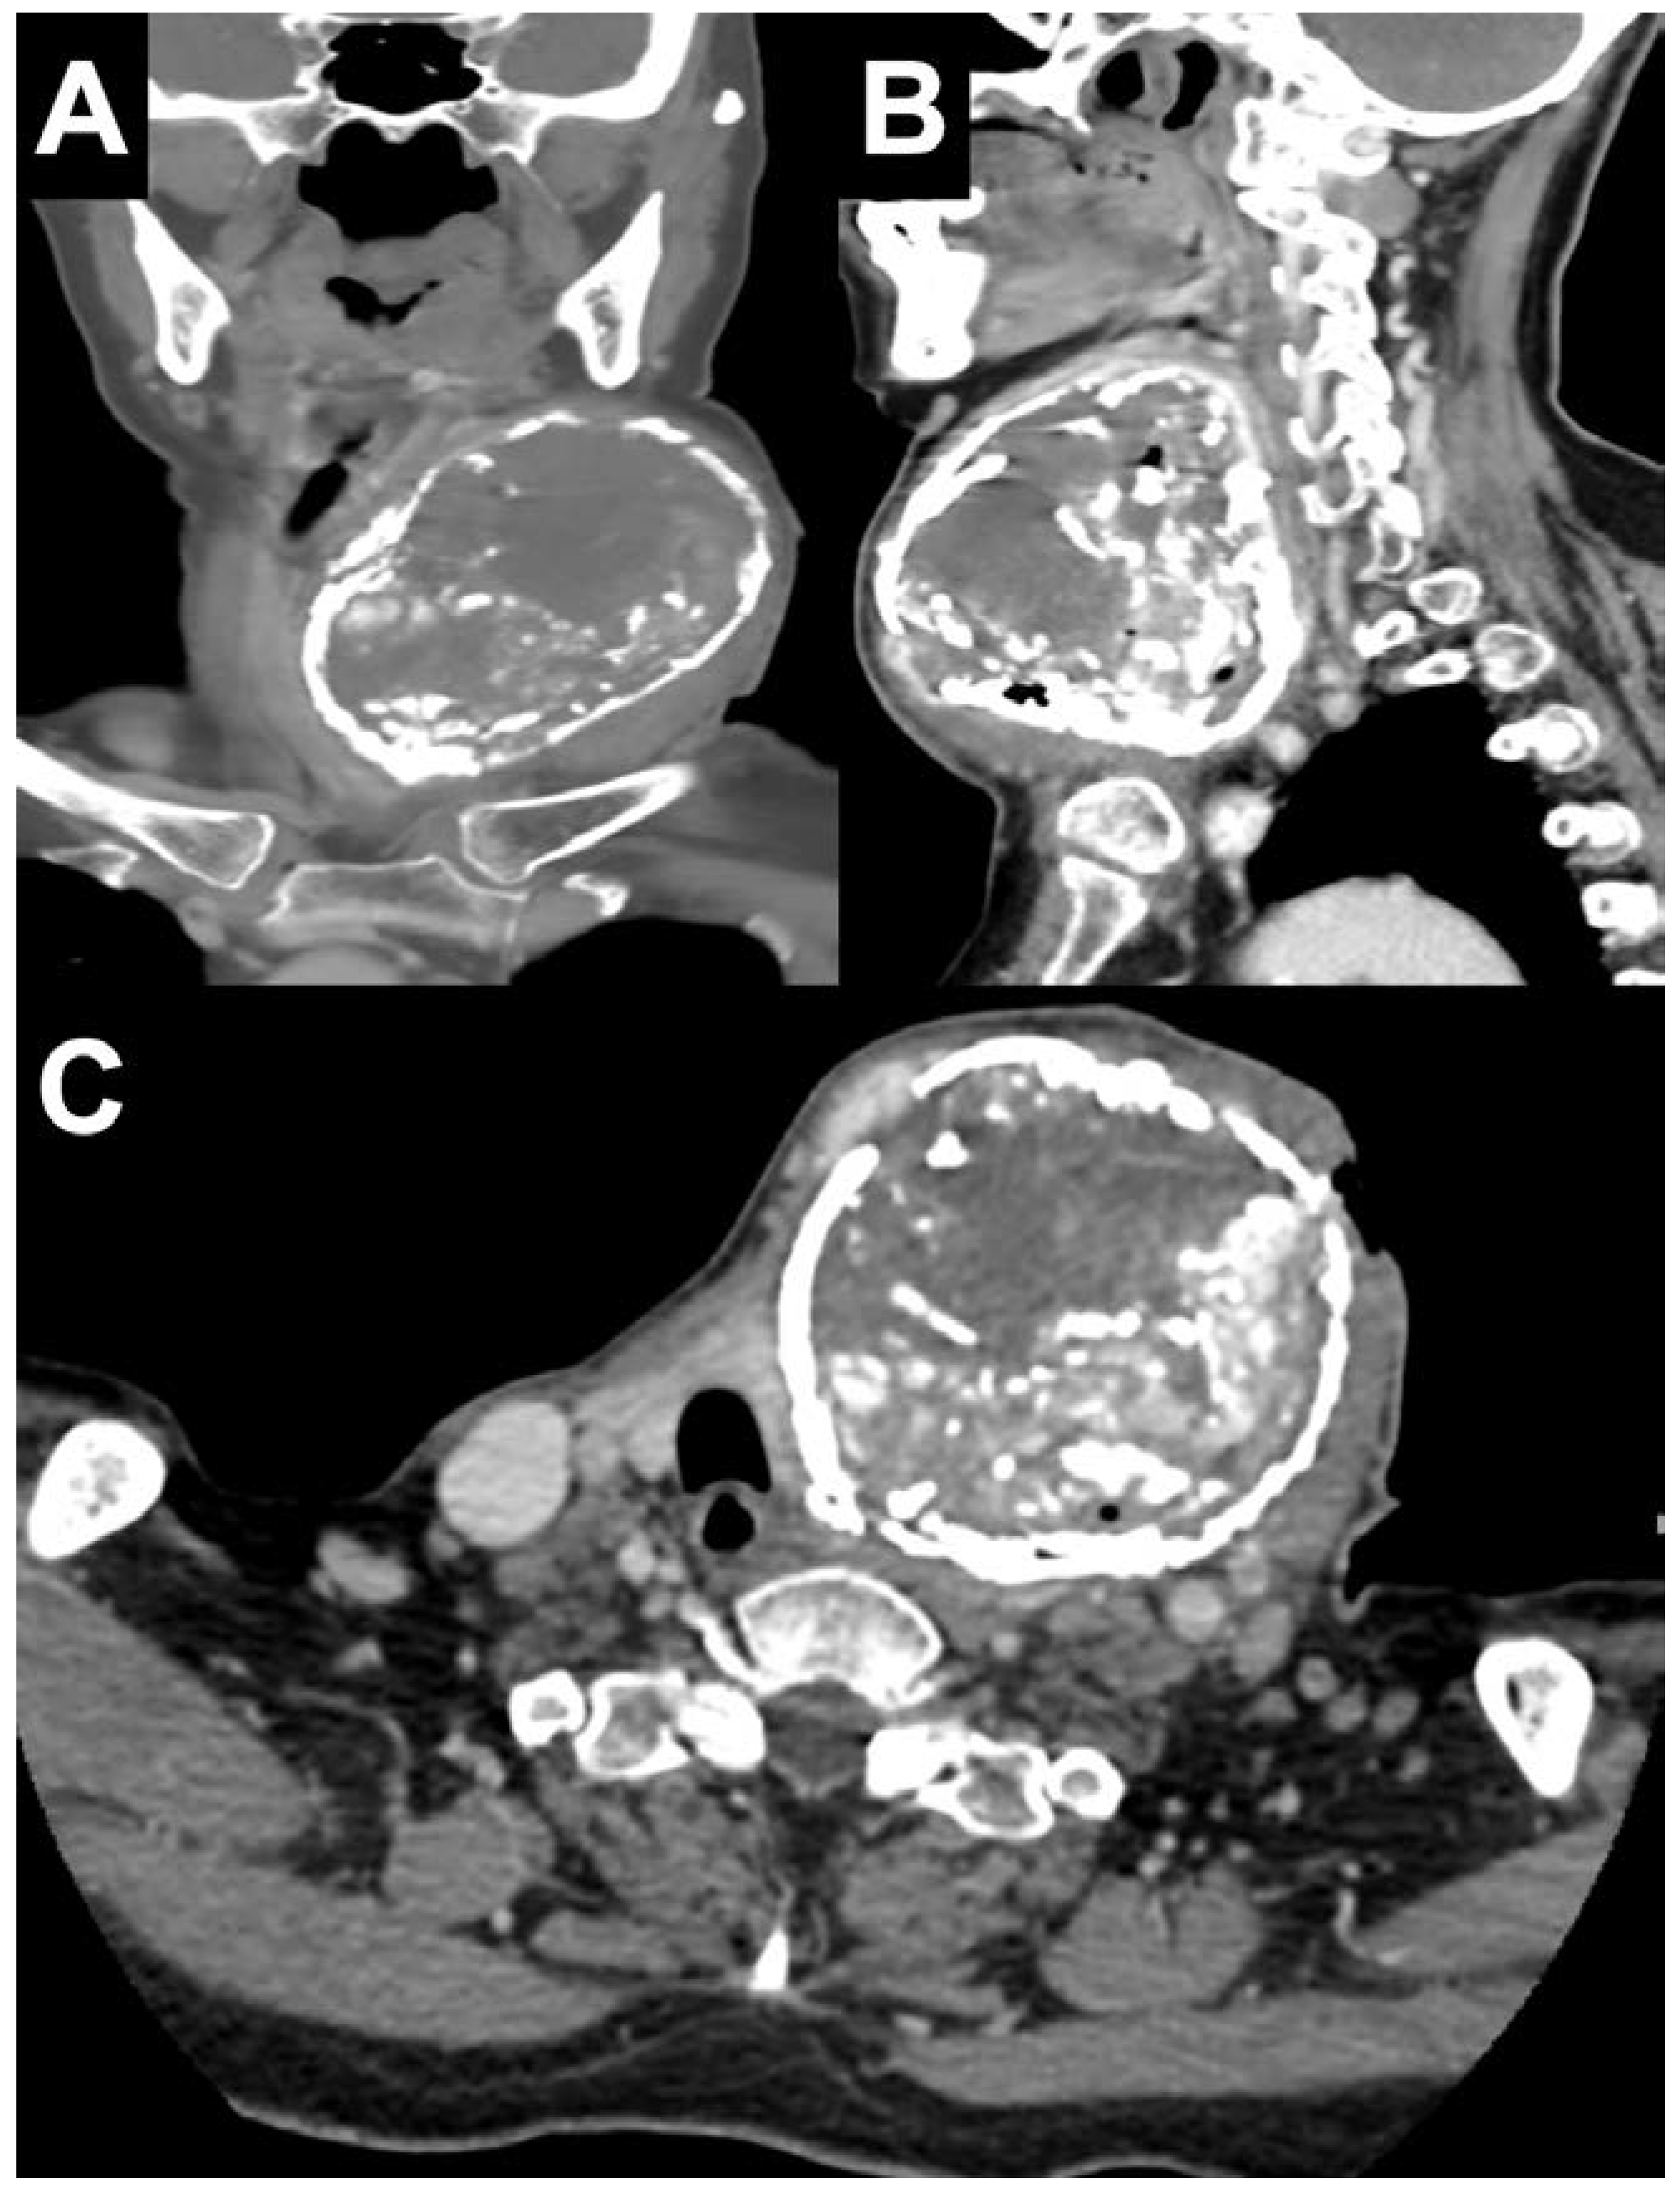

Initial investigations showed a white blood cell count of 7,550 cells/µL with neutrophils at 72%. Thyroid function tests were: free thyroxine (T4) of 0.82 (reference range, 0.70-1.48 ng/dL), free triiodothyronine (T3) of 2.46 (reference range, 1.88-3.18 pg/mL), thyroid-stimulating hormone (TSH) <0.0038 (reference range, 0.35-4.94 IU/mL), compatible with subclinical hyperthyroidism. The TSH receptor antibody was negative. The serologic test for HIV was negative. Her plasma glucose, renal, and liver function tests were within the normal reference ranges, except for low levels of serum albumin. Two blood cultures were negative. Computed tomography (CT) scan of the neck with contrast showed a heterogeneous enhancing mass with internal and rim calcification at the left lobe of the thyroid gland, measuring 8.4×7.2×9.7 cm (Figure 2). The lesion caused a pressure effect on the trachea and glottic larynx. The thyroid scan showed an uptake in the tilted horseshoe-shaped configuration corresponding to the functioning thyroid tissue in the periphery of the left enlarged thyroid mass and absence of uptake in the suppurative area (Figure 3).

Figure 2.

(A) Coronal, (B) sagittal, and (C) cross-sectional sections of computed tomography scan of the neck with contrast showed an 8.4×7.2×9.7 cm heterogeneous enhancing mass with internal and rim.